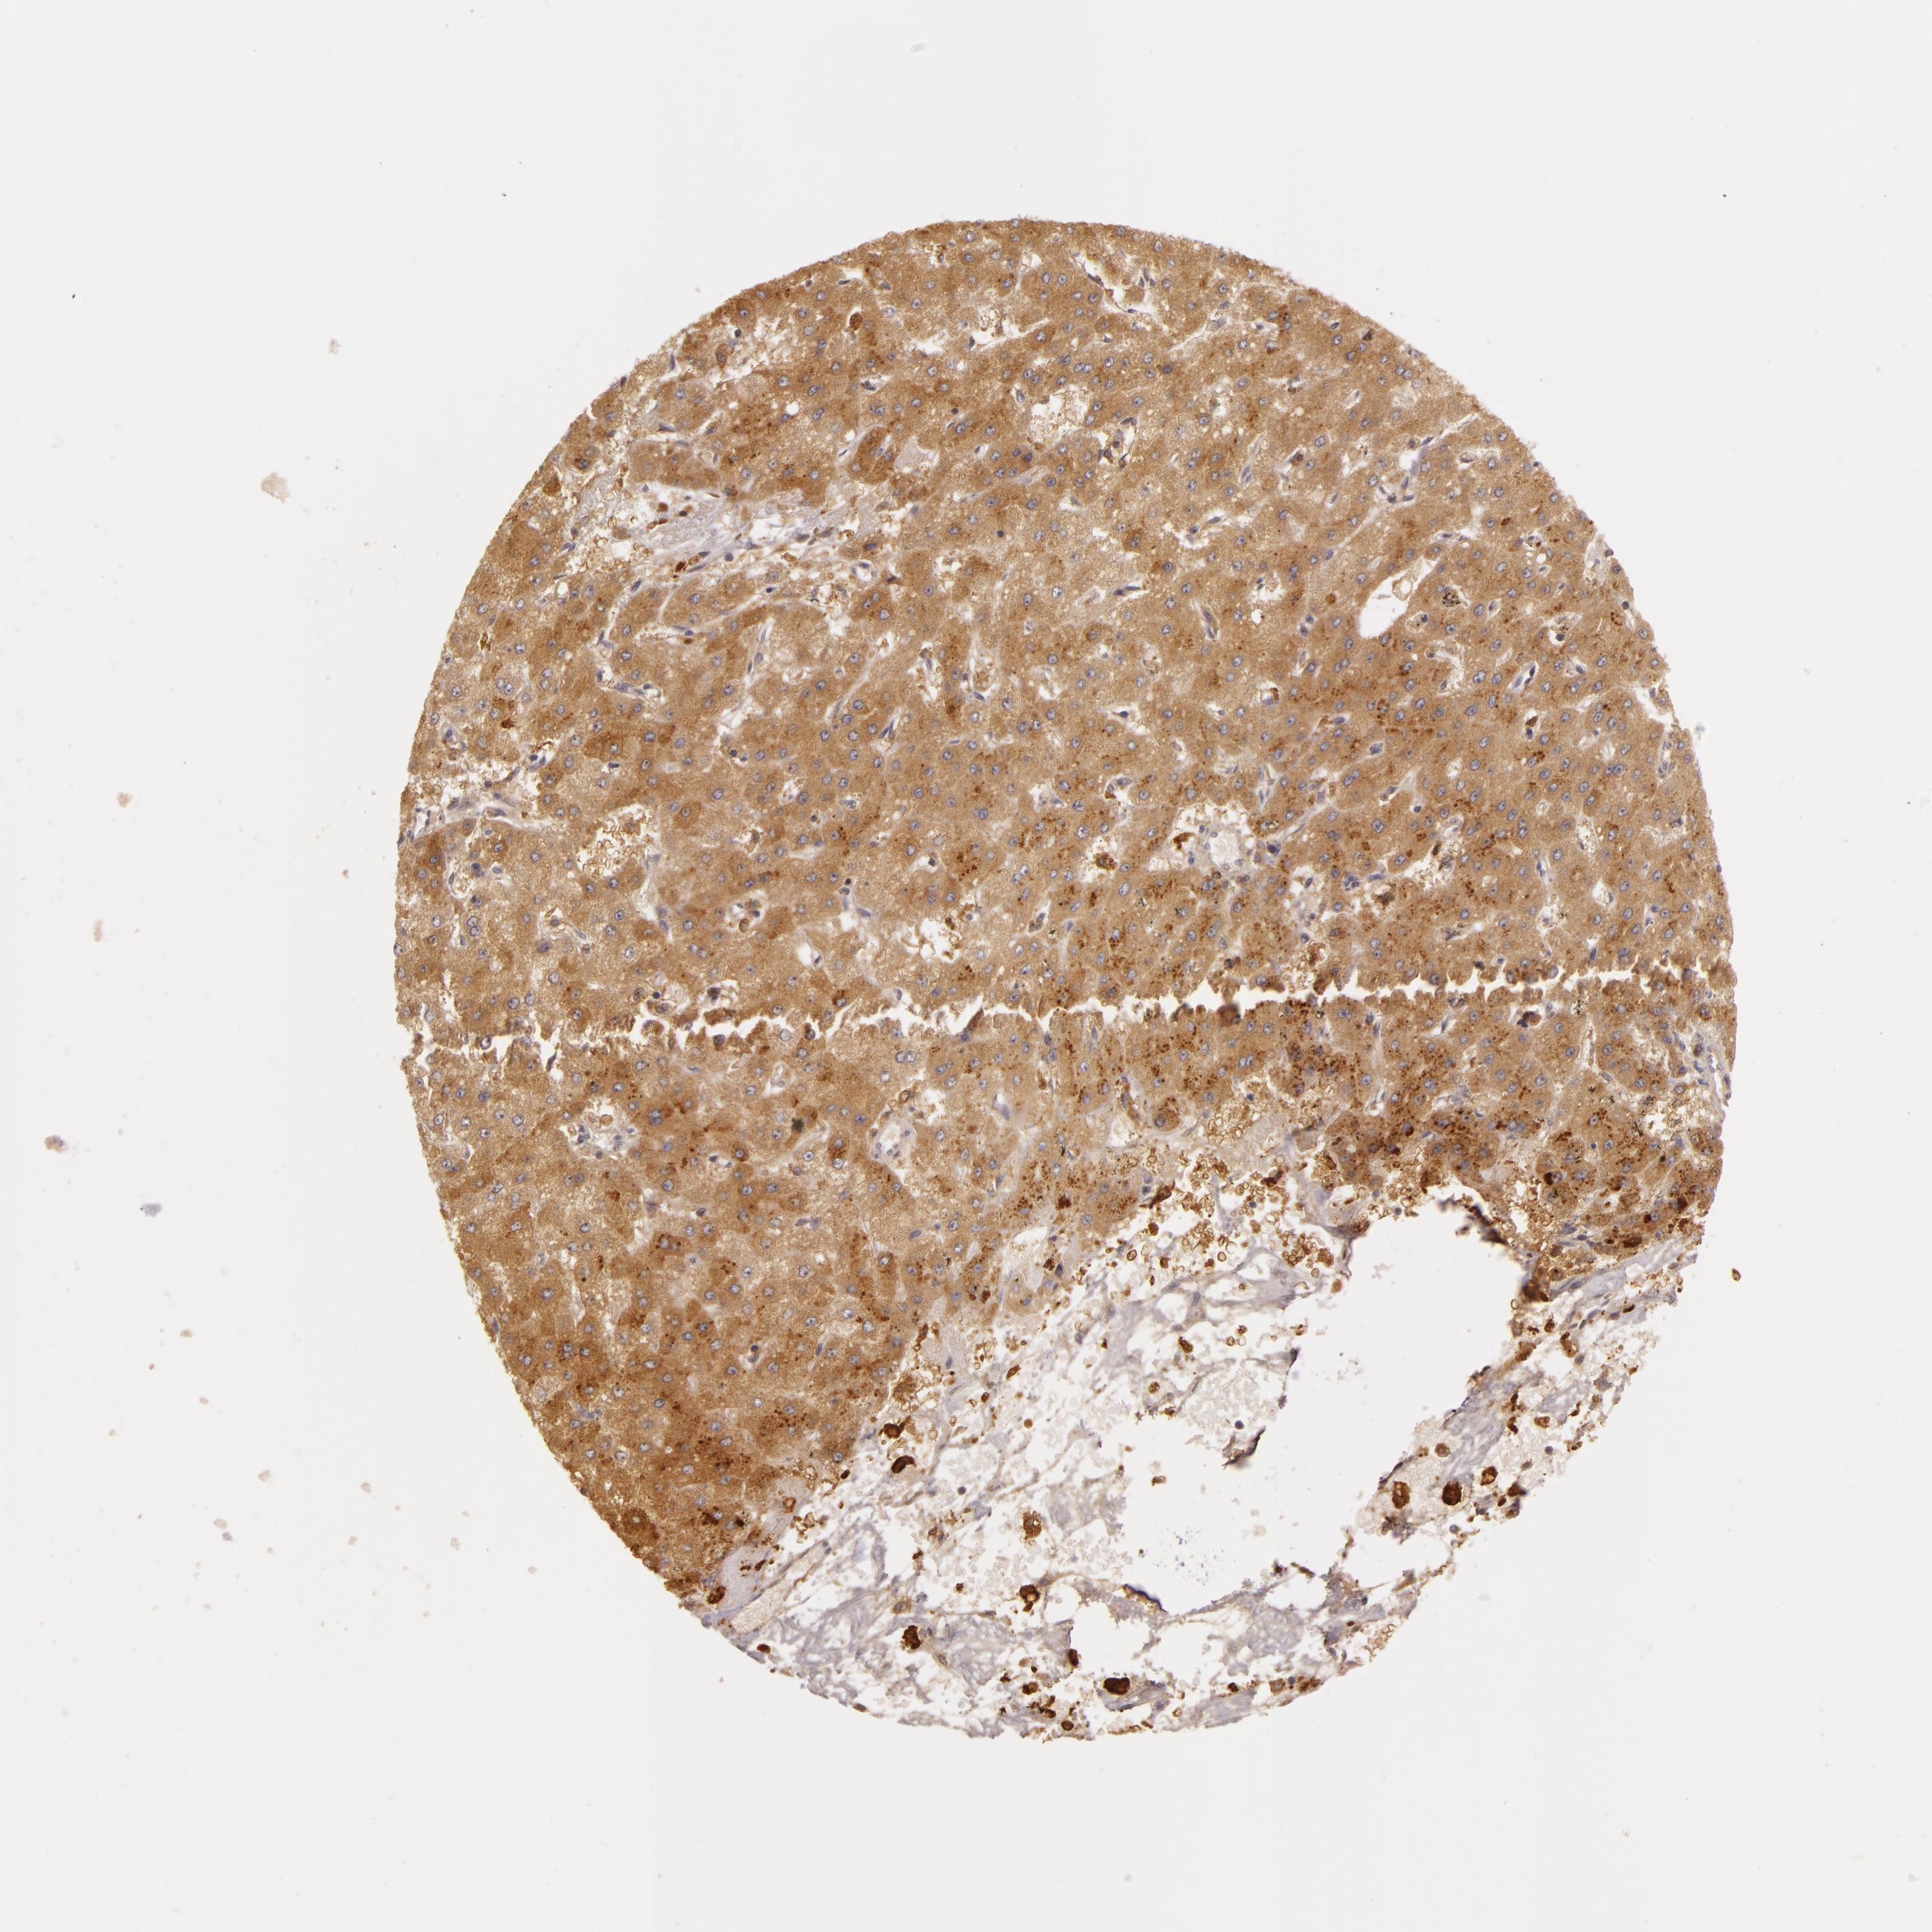

LIVER CANCER - Protein expressioni

A mouse-over function shows sample information and annotation data. Click on an image to view it in a full screen mode. Samples can be filtered based on level of antibody staining by selecting one or several of the following categories: high, medium, low and not detected. The assay and annotation is described here.

Note that samples used for immunohistochemistry by the Human Protein Atlas do not correspond to samples in the TCGA dataset.

Antibody stainingi

Antibody staining in the annotated cell types in the current human tissue is reported as not detected, low, medium, or high, based on conventional immunohistochemistry profiling in selected tissues. This score is based on the combination of the staining intensity and fraction of stained cells.

Each image is clickable and will lead to virtual microscopy that enables deeper exploration of all samples and also displays staining intensity scores, fraction scores and subcellular localization as well as patient and tissue information for each sample.

Antibody HPA000918

Staining

High

Medium

Low

Not detected

Intensity

Strong

Moderate

Weak

Negative

Quantity

>75%

75%-25%

<25%

None

Location

Nuclear

Cytoplasmic/membranous

Cytoplasmic/membranous,nuclear

Carcinoma, Hepatocellular, NOS